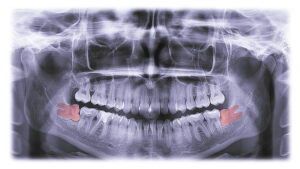

To plan their removal, we will examine the smile with digital x-rays, so we can assess their exact position in your bite. We then plan the extraction, so we can open the gums above them and access and remove these teeth with precision. This ensures we don’t encounter nerve tissues, blood vessels, or sinus cavities in the process. We also take steps to ensure you remain comfortable. For example, our team will numb the teeth with a local anesthesia and provide deep sedation, such as oral conscious sedation or IV, to help you enter a deep state of calm with no memory of the process at all. Even those with special needs or a fear of the dentist will be able to undergo care with comfort.

Let’s talk about the dangers posed by the presence of wisdom teeth. Typically, one tooth erupts at the end of each arch on the upper and lower portions of your smile. Some could have fewer erupt, some could have none at all. When you or a family member is approaching adulthood, then schedule an exam so we can look at the smile and assess the risks posed for your smile. If there is one, then we will gently remove these teeth before they erupt to protect the health, function, and appearance of your smile.

Otherwise, since there is simply no room for these teeth, they can cause teeth to shift to create misalignment, possibly undoing recent orthodontic progress! They may also only partially erupt, causing a painful impaction that is also linked to damaged teeth and infection.